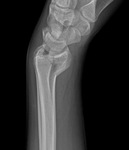

Wrist fractures

Posteroanterior radiograph showing malunion of the distal radius with significant shortening of the radius and relative lengthening of the ulna

From the collection of Dr Chaitanya S. Mudgal